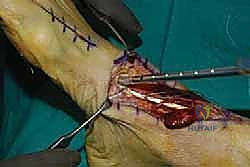

6. التثبيت العظمي المتين (Bone Fixation)

كيف نثبت الوتر الجديد؟ يقوم الأستاذ الدكتور محمد هطيف بحفر نفق عظمي دقيق في العظم الإسفيني الإنسي (Medial Cuneiform) في القدم. يتم إدخال وتر EHL داخل هذا النفق وتثبيته بقوة فائقة باستخدام إحدى التقنيات الحديثة:

* مسامير التداخل القابلة للامتصاص (Bio-absorbable Interference Screws).

* خطاطيف التثبيت العظمية (Suture Anchors).

يتم التثبيت والقدم في وضعية الانثناء الظهري الأقصى (مرفوعة للأعلى) لضمان الشد المناسب للوتر.

8. الإغلاق والتجبير

يتم إغلاق الجرح على طبقات باستخدام خيوط تجميلية، ثم توضع القدم في جبيرة خلفية أو حذاء طبي (CAM Boot) مع إبقاء الكاحل في وضعية الانثناء الظهري (مرفوع للأعلى) لحماية الوتر المنقول من أي شد مبكر.